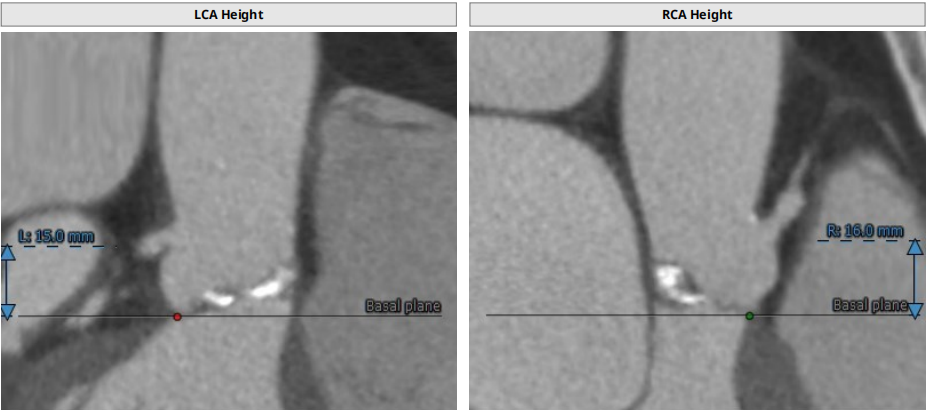

患者TYPE2型二叶瓣,左无、右无冠窦融合可能,左右部分粘连可能,轻度钙化,瓣叶增厚,法式窦结构不大,双冠高度可,升主动脉未见明显增宽,心脏角度不大,左室大,主动脉弓部走行较平缓,主动脉弓部、胸主动脉、腹主动脉可见多发钙化灶,操作需 谨慎。